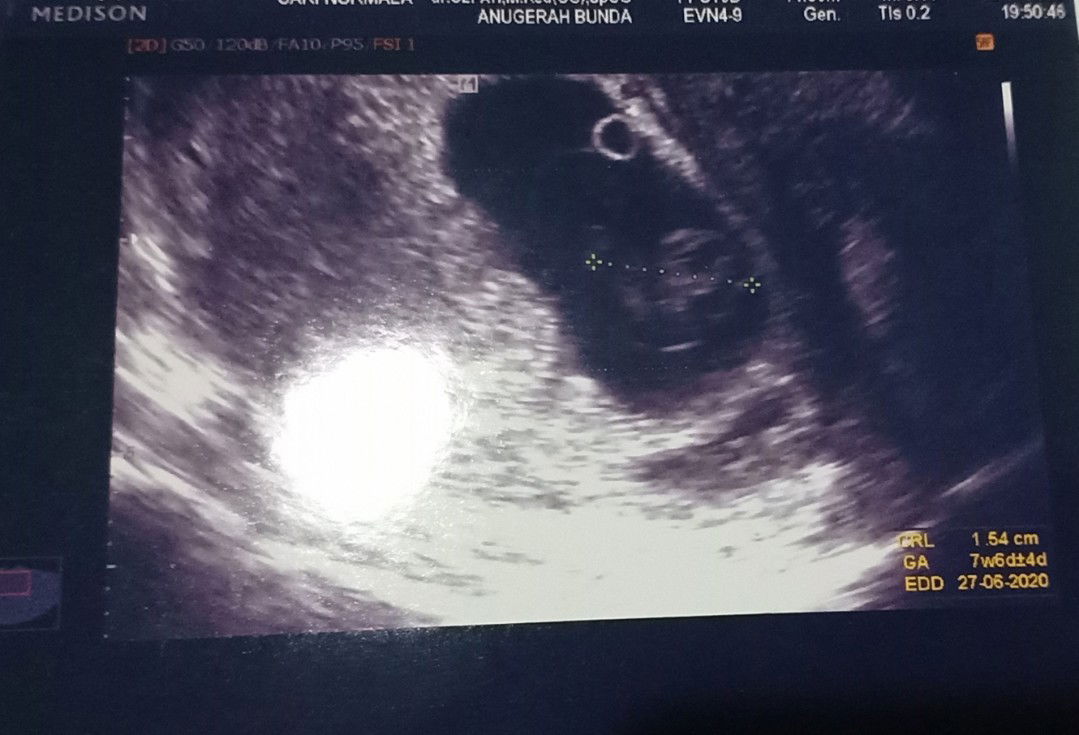

Mohon doa

HPHT 19-9-19 sudah Usg usia 7w6d. Alhamdulillah sehat, sudah ada janin dan terdengar detak jantungnya. Penantian 1 tahun pas. Mohon doanya supaya sehat sempurna sampe dan setelah lahiran yaa bunda